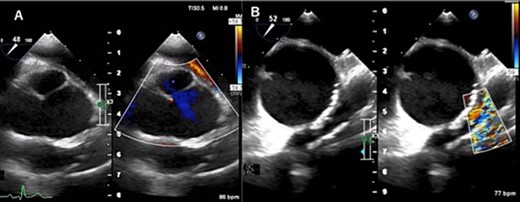

A 31-year-old man after the Ross procedure for congenital bicuspid aortic stenosis at 11-year-old was suffered from dyspnea on exertion. Transesophageal echocardiography revealed severe progressive right ventricular outflow tract (RVOT) stenosis and mild aortic regurgitation with autograft root dilatation (Fig. 1). Subsequently, the catheter exam showed 55 mmHg pressure drop in RVOT. The cardiac CT demonstrated mildly dilated autograft root with the diameter of 42 mm and small size RVOT conduit. The four-dimensional flow magnetic resonance imaging revealed the presence of mild aortic valve regurgitation and severe pulmonary valve regurgitation, with a regurgitant fraction of 34.4% (Fig. 2). The RVOT reconstruction concomitant with the valve sparing root reimplantation was planned, because of concerns regarding root dilation of the autograft in response to left ventricular volume load increase.

Transesophageal echocardiogram captured preoperatively shows a dilated sinus of Valsalva and mild central aortic valve regurgitation (A), and severe RVOT stenosis (B).